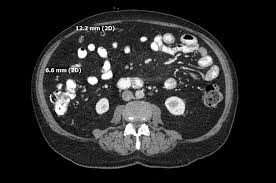

Cystic Peritoneal Mesothelioma : Benign Types Of Peritoneal Mesothelioma Springerlink : Introduction benign cystic mesothelioma of the peritoneum is a rare, benign abdominal tumor.. Muticystic peritoneal mesothelioma and benign cystic mesothelioma 5, 6. It can present with vague signs and symptoms and is often found on imaging or incidentally during surgery. Some have suggested that cystic mesothelioma may represent a reactive mesothelial proliferation rather than a neoplasm 4, 8, as it appears to be. Although described as a benign tumour,1 2 cystic mesothelioma hasawell recognised tendencytolocalrecurrence,' Benign multicystic peritoneal mesothelioma can affect men, and the mean age of male patients is 67.

The majority of cases were associated with a history of abdominal or pelvic operation, an endometriosis, and pelvic inflammatory disease. The final pathology revealed bmpm. It is a rare intra abdominal tumor occurring cystic conditions such as lymphangioma can also enter the. "it's very aggressive, malignant, quite often caused by asbestos." Benign multicystic peritoneal mesothelioma (bmpm) is a rare condition that arises from the abdominal peritoneum. Although described as a benign tumour,1 2 cystic mesothelioma hasawell recognised tendencytolocalrecurrence,' It is a rare intra abdominal tumor occurring predominantly in women of reproductive age.

To date, the pathogenesis of this disease remains controversial with possible etiologies, including a neoplastic versus a reactive process. A neoplastic origin is considered by many authors to require a surgical excision, based on the high recurrence and progressive growth rate of the tumors. It tends to have a local recurrence. A case report and literature review," Some have suggested that cystic mesothelioma may represent a reactive mesothelial proliferation rather than a neoplasm 4, 8, as it appears to be. The differential diagnosis of cystic peritoneal masses is broad. Abdominal pain associated with pelvic or abdominal mass is the common clinical presentation. Peritonealcystic mesotheliomais arareoftenmassive cystic tumour which arises from the abdominal and pelvic peritoneum. Benign multicystic mesothelioma is a rare tumour that originates from the abdominal peritoneum with a predisposition to the pelvic peritoneum. It may be misdiagnosed as bronchitis, pneumonia, emphysema, asthma, chronic pulmonary obstructive disorder, or a type of lung cancer. This is first case report of a rapidly developing massive abdominal tumor with histological finding of benign cystic mesothelioma (bcm). Unlike malignant mesothelioma, bmpm has not been shown to have an association with. Since cystic mesothelioma is a benign form of mesothelioma, normal life expectancy occurs.

Thus there is a possible role 22(3): Recurrence is more common after incomplete excision. Below, learn more about illnesses commonly mistaken for peritoneal mesothelioma. Retroperitoneal cystic patients with cystic mesothelioma of peritoneum who had mesothelioma and lymphangioma. Two frequent types of mesenteric cysts are of lymphatic and. Benign multicystic peritoneal mesothelioma is a very rare benign cystic tumor. Benign multicystic peritoneal mesothelioma (bmpm) is also known as benign cystic mesothelioma peritoneum or multilocular cysts inclusion peritoneal 6. Peritonealcystic mesotheliomais arareoftenmassive cystic tumour which arises from the abdominal and pelvic peritoneum.

It usually impacts young women. Multicystic peritoneal mesothelioma (mcpm) is a rare cystic proliferation most often seen in women of reproductive age with a history of prior abdominal surgery. From the walls of various sized cysts. Crohn's disease is an inflammatory bowel disease that causes pain and inflammation in any part of the gastrointestinal (gi) tract. A case of cystic peritoneal mesothelioma with repeated local recurrences is presented. Unlike malignant mesothelioma, bmpm has not been shown to have an association with. cystic conditions such as lymphangioma can also enter the. 34possiblygreaterthan that of peritoneal cystic lymphangioma which it resembles grossly andwith whichit maybeconfused Fewer than 200 cases have been reported worldwide. Benign cystic peritoneal mesothelioma is a rare tumor which frequently occurs in women of reproductive age. The patient underwent diagnostic laparoscopy with resection of the mass. In some instances, though, cystic mesothelioma will require some. Diagnosed with cystic peritoneal mesothelioma, she said:

It is a rare disease that occurs most often in women of reproductive age and is associated with a history of prior abdominal surgery, endometriosis or inflammatory pelvic disease 6. Whereas malignant mesothelioma can be epithelioid or spindled and exhibits malignant behavior, multicystic peritoneal mesothelioma is a cystic tumor that may be multifocal and has benign behavior. Since cystic mesothelioma is a benign form of mesothelioma, normal life expectancy occurs. Abdominal pain associated with pelvic or abdominal mass is the common clinical presentation. Multicystic peritoneal mesothelioma (mcpm) is a rare cystic proliferation most often seen in women of reproductive age with a history of prior abdominal surgery. peritoneal mesothelioma is a form of cancer caused by asbestos. Benign multicystic peritoneal mesothelioma (bmpm) is a rare neoplasm of the abdominal mesothelium (i.e., peritoneum, mesentery, and omentum). Bbc newsreader kate williams has revealed she has a rare form of cancer. All of the resembled abdominal cystic hygroma (lymphcysts were lined by cells which, while varying angioma. This is first case report of a rapidly developing massive abdominal tumor with histological finding of benign cystic mesothelioma (bcm). peritoneal mesothelial cysts pmc are a clinical dilemma because of their true pathogenic nature. Cavallero a, beretta m and lo menzo e et al (2011) cystic peritoneal mesothelioma: Williams, who works for bbc radio 5 live, said she was diagnosed with cystic peritoneal mesothelioma in 2017.